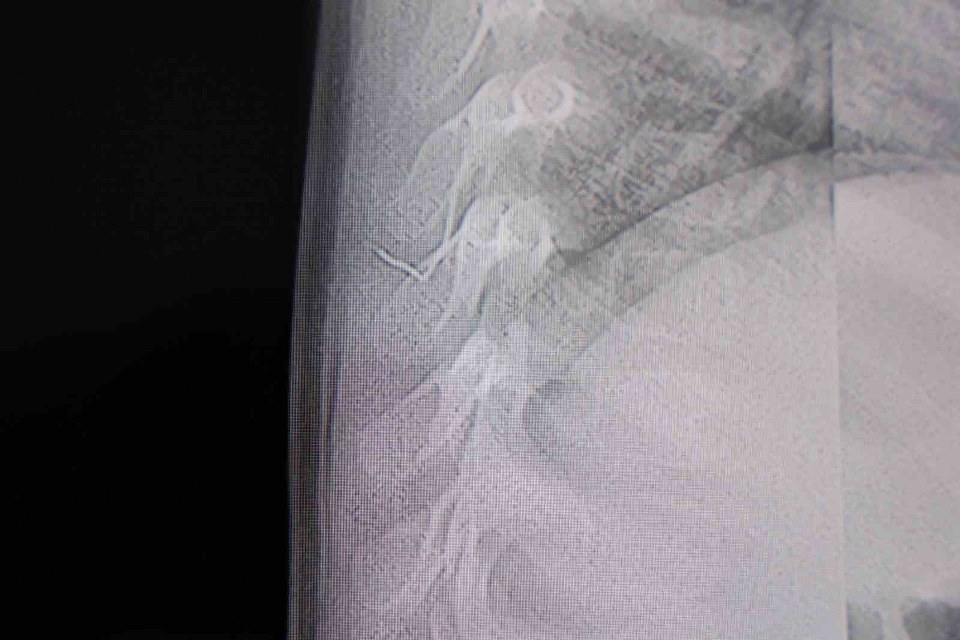

Alınan bilgiye göre, Kahramanmaraş’ta farklı ortopedi, çocuk cerrahisi ve beyin cerrahisi kliniklerine başvurusu yapılan bir yaşındaki bebeğin, sırt bölgesinde yabancı bir cisim olduğu ancak müdahalenin zor olduğu ve 8 yaşına kadar beklenmesi gerektiği bildirildi. Aile, bebekleri için son olarak HG Hospital’e başvurdu. HG Hospital Beyin ve Sinir Cerrahisi Uzmanı Prof. Dr. İdris Altun tarafından yapılan tetkiklerde, yabancı cismin cilt altında, omurilik kanalına yakın bir bölgede olduğu ve akciğer zarına doğru ilerlediği belirlendi. Hasta, genel anesteziye alınmadan, lokal anestezi ve sedasyon eşliğinde ameliyata alındı. Yapılan müdahalede yabancı cisim tamamen çıkarıldı. Çıkarılan cismin, ince zımba teline benzer metal bir tel olduğu ve yaklaşık 2 santimetre uzunluğunda bulunduğu tespit edildi. Hasta, aynı gün taburcu edildi.

Konuya ilişkin açıklama yapan Prof. Dr. İdris Altun, “Sırtında yabancı bir cisim olduğu söylenmiş ancak çıkarılamayacağı ve 8 yaşına kadar beklenmesi gerektiği ifade edilmişti. Bize başvurduğunda yaptığımız tetkiklerde, cilt altında, omurilik kanalına çok yakın ve akciğer zarına doğru ilerleyen bir yabancı cisim tespit ettik. Hastamızı tamamen uyutmadan, lokal anestezi ve sedasyon eşliğinde müdahale ederek lezyonu tamamen çıkardık. Çıkardığımız cismin ince zımba teline benzer, yaklaşık 2 santimetre uzunluğunda metal bir tel olduğunu gördük. Bu yabancı cisim alınmasaydı, bölgede enfeksiyon gelişebilirdi. Enfeksiyon sonucu omurilik kanalında ciddi hasarlar oluşabilir, çocuk büyüdükçe cismin hareket etmesine bağlı olarak omurilikte zedelenmeler meydana gelebilirdi. Ayrıca yana doğru ilerleyerek akciğer zarına ve akciğere batma riski vardı. Bu da enfeksiyona ve ilerleyen süreçte tümörle karışabilecek tablolara neden olabilirdi. Şu an hastamız gayet sağlıklı. Gerekli kontrolleri yaptık ve aynı gün taburcu ettik” dedi.